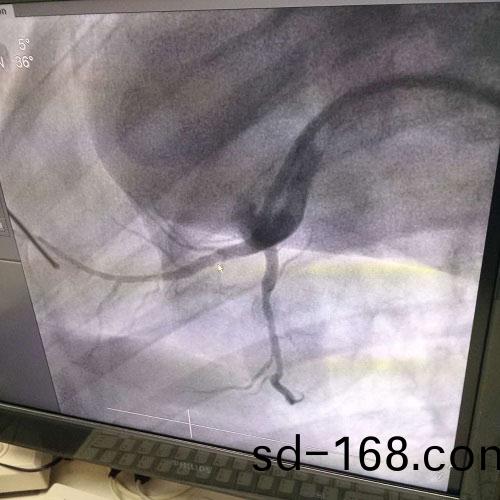

�������������ִ�ҽ�Ƽ����ķ�չ��ҽ���豸���������ƣ�������֧�������Ѿ���Ϊ������Ѫ���Ʒ���һ����Ҫ�ֶΡ�Ѫ�ܽ��뼼������ҽѧӰ���豸�ĵ����£����ô����롢��˿�����ܵ���е��Ѫ��;���������������ƵIJ����������Ѿ���Ϊ���Ƹ���Σ�����ཡ�����������ѷ���֮һ��

Ŀǰ���ٴ���Ӧ�õ�֧�������ܶ࣬����֧�ܵIJ��ʶ�Ϊ�����֡���-�ѺϽ�����-���Ͻ��Ƚ�������Щ����֧�ܶ����������Եģ�����������Ĥ��������֢��Ӧ�ȡ�Ϊ������ͳ����֧�ܵľ����ԣ����ÿɽ���Ѫ��֧�ܿ��Ժܺõؽ�����ͳ����֧�ܴ��ڵ��������⡣þ�Ͻ����������˵���ѧ���ܡ���֯�����ԡ�����˨�ԡ������Ե��ŵ�����Ϊ�ɽ���֧�ܵ���ѡ���ϡ�

����ȫ����þ�Ͻ�ҩ��ϴ��֧�������ɹ�˾���������з�����Ҫ���ռ�����ȫ������������ȫ����֪ʶ��Ȩ�����ҿ�����ǿ��ǰ���з�������ʵ���г��������У�ʵʩ���տɿأ���ȫ��ͬ��ҵ���ȼ���������ڼ�����չ�հף����Ϲ��Ҳ�ҵ��չ���ߣ����ᡢ����Ч������Ŀǰþ�Ͻ�ҩ��֧���ѽ��붯��ʵ���Σ�ֲ�붯������һ����֮��Ч�����á�